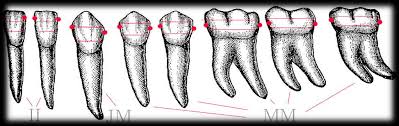

Maradó fogazat

Ideális esetben 32 fogból áll a maradó fogazat. A 32 fogat 4 negyedre (kvadránsra) osztjuk fel, jobb felső és bal felső, valamint bal alsó és jobb alsó. Tehát minden kvadránsban 8 fog található: 3db nagyőrlő, 2db kisőrlő, 1db szemfog és 2db metszőfog.